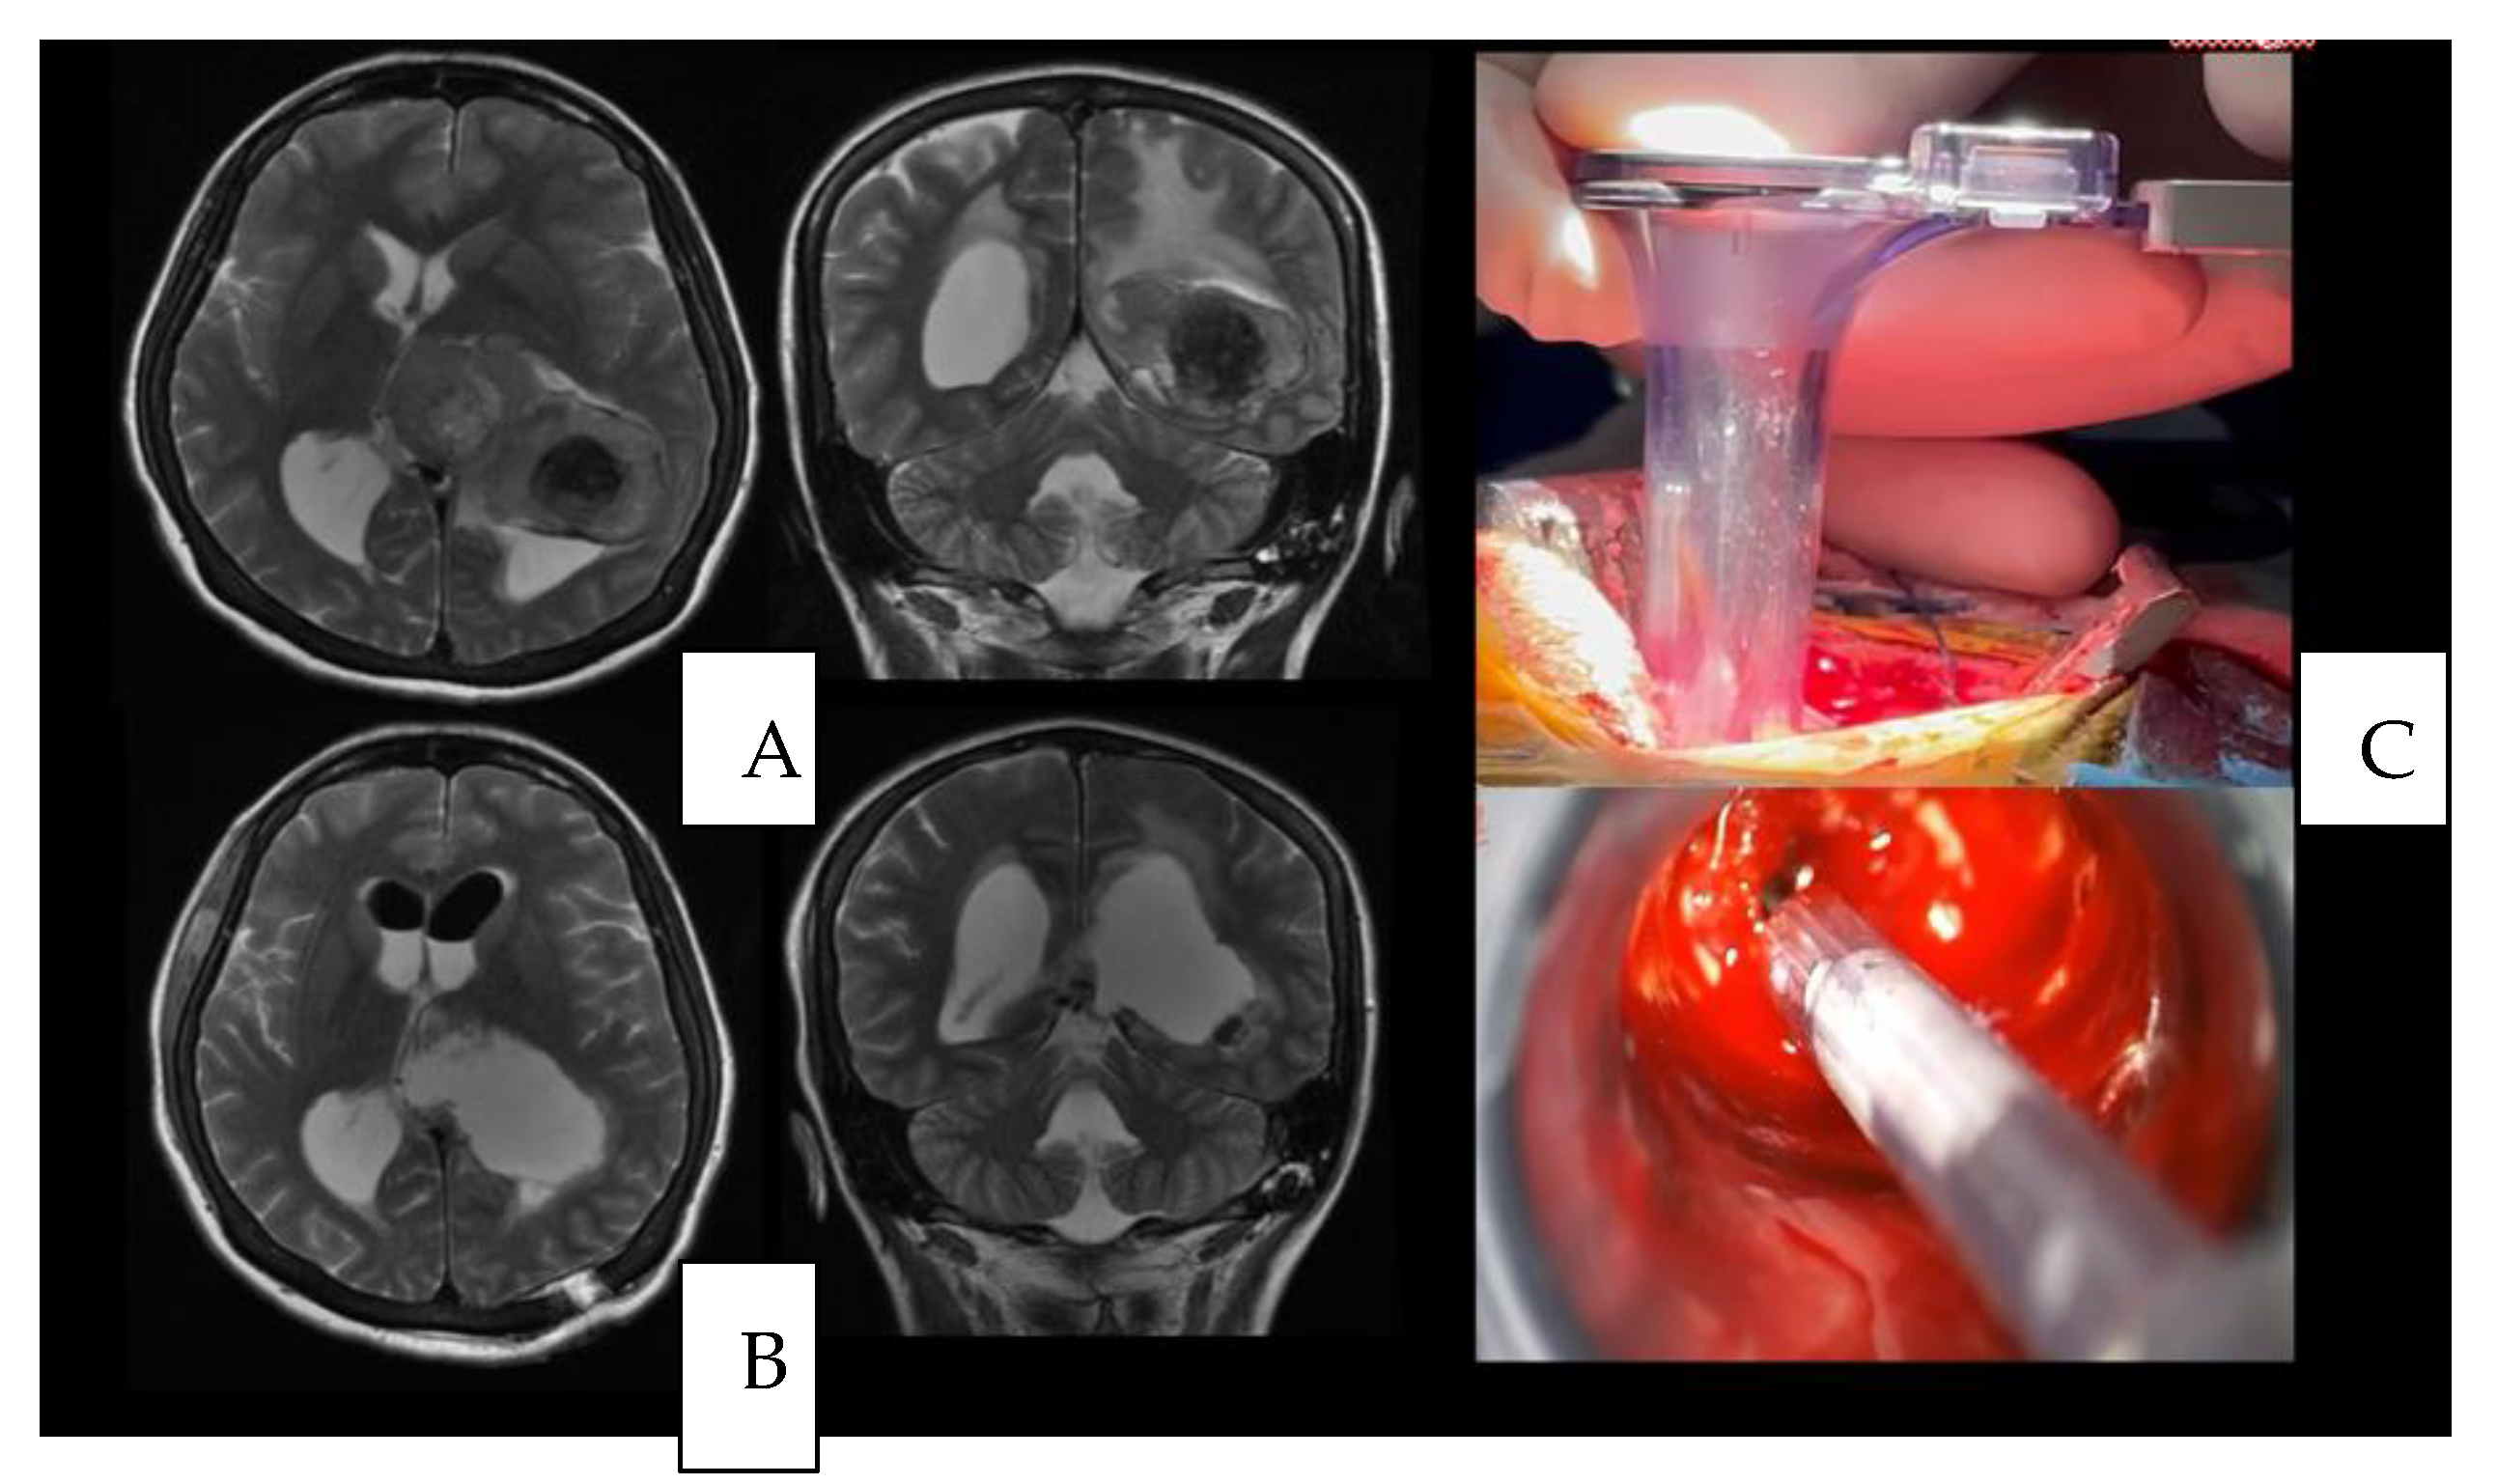

4.1. Case 1

4.3. Surgical Nuances